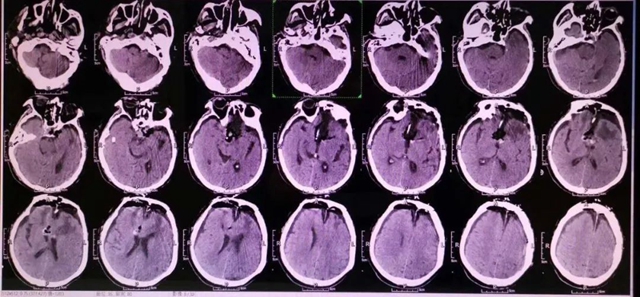

2020年,四川省自贡市70多岁的付大爷突然昏迷,摔伤额头,当地医院头颅CT发现颅内存在巨大占位性病变,转入西南医科大学附属中医医院神经外科进一步诊治,头颅MRI显示脑袋正中偏左的鞍区处有一个“胎儿”样的巨大肿瘤。

由于鞍区肿瘤与周围脑组织特别是下丘脑紧密相邻手术难度很大,一般难以全切,术后复发率高。

术前

术后

神经外科手术团队针对肿瘤位置和术后康复多次术前讨论,反复思考手术入路。

较好的显露鞍区及鞍旁组织结构,针对术后易出现内分泌紊乱、低钠血症等问题认真分析,制定精细的康复治疗方案。即行神经颅内镜辅助显微镜下鞍区巨大占位切除术,历时6小时,肿瘤被完全切除,解除了肿瘤对视神经、视交叉及其他神经、血管的压迫。

术后一周后,付大爷双眼视力逐渐好转,各项生命体征平稳。家属感叹不已:“4年来,老人视力越来越差,经常头晕头痛,一直认为是白内障,现在终于放心了。”